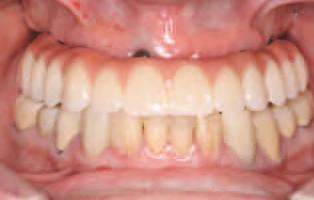

15. Vedere extraorală a restaurărilor finale livrate.

16. Vedere intraorală a restaurărilor finale mandibulare livrate.

În cab net, restaurăr le prov zor au fost deșurubate ș îndepărtate d n cav tatea orală pentru ca restaurăr le f nale să poată f l vrate ș strânse cu un cuplu de 15 Ncm, conform recomandăr producătorulu (f g. 15,16). Ajustăr le ocluzale f nale au fost m n me ș efectuate ntraoral pr ntr-o ultmă lustru re a zonelor ajustate.